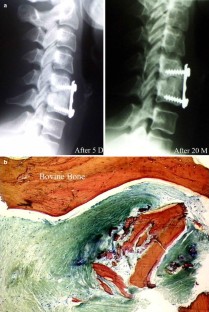

Few histological studies on bone substitutes in human cervical spine are available and the biological processes of bone substitutes are not well documented. The authors studied four failure cases of cervical interbody fusion: two cases with hydroxyapatite (HA), one case with β-tricalcium phosphate ceramic (β-TCP) and one case with xenograft (bovine bone). Clinical data showed that all the patients experienced neck pain with or without numbness of upper extremity due to fusion failure. Successful fusions were achieved after the salvage surgeries in which autograft were used. Radiographs showed that radiolucent lines were present in all cases. Two HA substitutes fractured without complications. One of them sank into the vertebral body. Some small β-TCP fragments were found under the microscope. Histological study demonstrated only a few newly formed bones at the interface of the substitutes. The fragments of HA were encapsulated by fibrous tissue. The degradation process and bone regeneration were more active in β-TCP than in HA. The intertrabecular spaces of bovine bone were filled with fibrous tissue. The results suggest that a porous calcium phosphate ceramic with special design might assure bone ingrowth and meet the mechanical requirements in cervical interbody fusion. The complications of these materials in the cervical spine should be highlighted.

Fig. 3